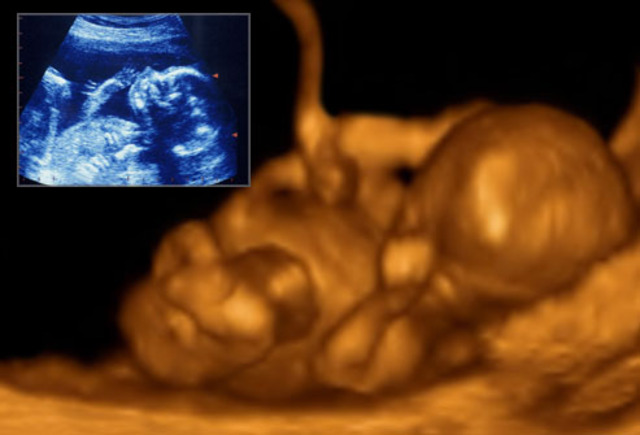

20 weeks pregnant

The baby is starting to move around. Also his hair, nails are stilling growing. Also the babys limbs are developed. That is what 20 weeks pregnant.